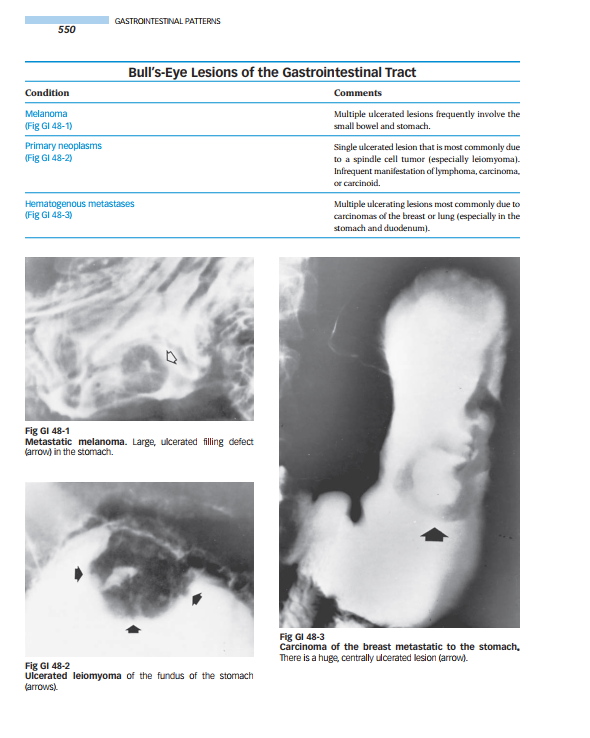

Organized by anatomic area, the book outlines and illustrates typical radiologic findings for every disease in every organ system. Tables on the left-hand pages outline conditions and characteristic imaging findings…and offer comments to guide diagnosis. Images on the right-hand pages illustrate the major findings noted in the tables.